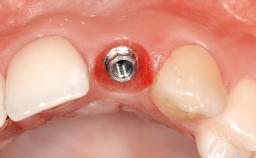

In September of 1995, a 64-year-old female patient presented to our clinic with a distally shortened arch in the left maxilla and the desire for a fixed rehabilitation. The patient’s medical history did not reveal any major issues, and she did not take any significant medication. She was a non-smoker and did not report any allergies.The patient wished to restore her chewing function on the left side, which was severely compromised due to the missing teeth 25, 26, and 27. The antagonistic lower teeth were present and in acceptable condition.